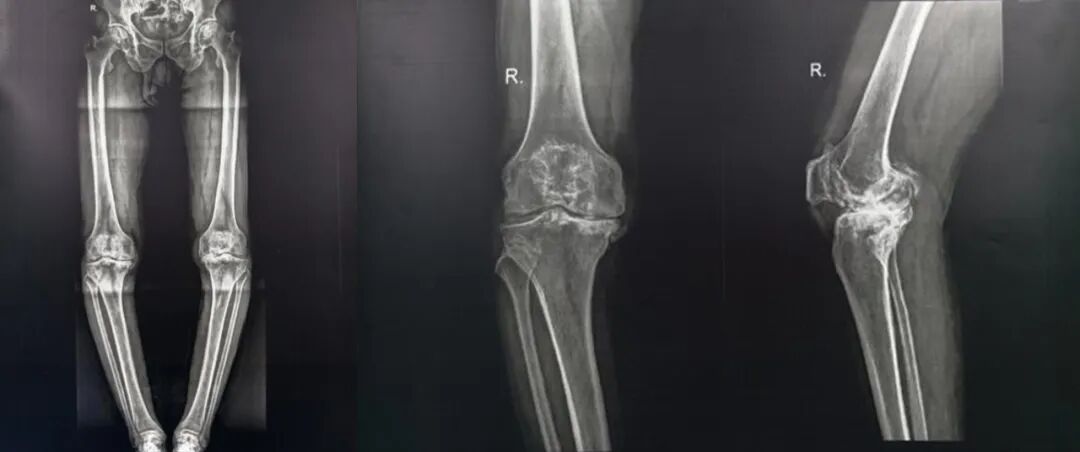

首台机器人辅助全膝关节置换手术

患者裴某,男性,66岁,患双膝关节疼痛长达20年之久,症状在行走及体力活动后显著加剧,慕名前往佳木斯骨科医院关节外科王忠春教授门诊就诊。经诊断,确诊为“双侧膝关节骨性关节炎”,鉴于其病程漫长并伴有一定程度的关节畸形,加之骨质状况不佳,王忠春教授及其团队决定采用机器人辅助手术技术进行辅助手术。

医疗团队充分利用了机器人的智能手术规划系统,根据患者的个体特征进行了精准的手术规划,并利用ARTHROBOT可视化、数字化和精准化的优势,通过实时导航系统辅助定位,仅用20分钟完成膝关节精准截骨和假体安装,假体安装位置与规划完全一致,完全实现了功能力学定线,并实现了内外侧和伸屈间隙完全平衡,手术全程出血量少,软组织干扰小,操作时间较传统手术明显缩短。